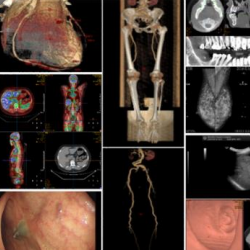

支持DICOM与非DICOM影像,支持多平面重建、曲面重建、容积重建、动态分析和视频采集。

智能化报告

根据描述自动生成诊断。自动审核报告质量和报告完整性,减少误诊与漏诊。